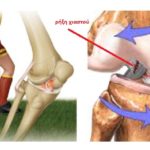

Στατικά το γόνατο σταθεροποιείται από 4 μείζονες συνδέσμους: τους 2 χιαστούς συνδέσμους (πρόσθιο και οπίσθιο) και τους 2 πλαγίους συνδέσμους (έσω και έξω). Οι 2 χιαστοί σύνδεσμοι οφείλουν την ονομασία τους στο γεγονός ότι διασταυρώνονται μεταξύ τους στο κέντρο του γόνατος σε σχήμα «Χ» (εικόνα 1 ). Λειτουργούν ως σύστημα, το οποίο αποτρέπει την προσθιοπίσθια αστάθεια και τη στροφική αστάθεια κατά την κίνηση της άρθρωσης. Οι 2 πλάγιοι σύνδεσμοι, εμποδίζουν την αστάθεια σε μετωπιαίο επίπεδο. Εμποδίζουν δηλαδή το «άνοιγμα» του γόνατος προς τα μέσα ή έξω. Σε κάθε πλευρά (έσω – έξω) της αρθρώσεως, 2 σφηνοειδείς και σχετικά ανελαστικές σχήματος C ινώδεις δομές παρεμβάλλονται μεταξύ του μηρού και της κνήμης, ο έσω και ο έξω μηνίσκος ( εικόνα 1 ).

Ο κύριος ρόλος των μηνίσκων είναι η απορρόφηση των φορτίσεων, συμβάλλουν ωστόσο και στη σταθερότητα και την επαρκή λίπανση της άρθρωσης. Πρέπει να τονισθεί ότι όπως σε όλες τις αρθρώσεις, έτσι και στο γόνατο, η σταθεροποίηση διακρίνεται σε δυναμική και στατική. Σε απλές καθημερινές συνθήκες η σταθεροποίηση είναι δυναμική και επιτυγχάνεται από τις μυϊκές ομάδες πέριξ του γόνατος, πχ τετρακέφαλος μυς. Σε περιπτώσεις όμως ταχείας ή βίαιης επαπειλούμενης παρεκτόπισης, αναλαμβάνουν οι στατικοί σταθεροποιητές, οι σύνδεσμοι δηλαδή που προαναφέραμε. Από το γεγονός αυτό μπορεί κάποιος να αντιληφθεί πόσο σημαντική είναι για τη σταθερότητα του γόνατος αλλά και την «προστασία» των συνδέσμων του η άριστη κατάσταση του μυϊκού συστήματος που κινεί την άρθρωση. Ιδιαίτερα μάλιστα όταν μιλάμε για αθλητές και μάλιστα ανταγωνιστικού επιπέδου! Είναι επίσης κατανοητό ότι το ίδιο σημαντική είναι η μυϊκή ενδυνάμωση μετά από συνδεσμικές κακώσεις ή επεμβάσεις αποκατάστασης μηνισκικής βλάβης ή ρήξης χιαστού.